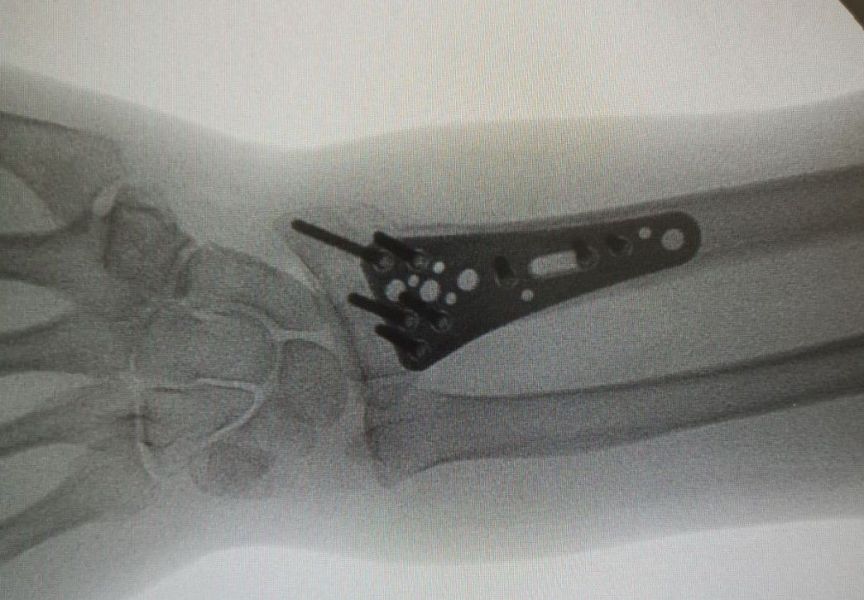

4. Displaced fracture of distal end of the right radius (wrist fracture) in a 63-year-old female.

Treatment. Open reduction internal fixation

I. Before operation, anteroposterior x-ray of the wrist II. Before operation, lateral x-ray of the wrist IIA. Day of procedure, lateral view IIB. Day of procedure, anteroposterior view